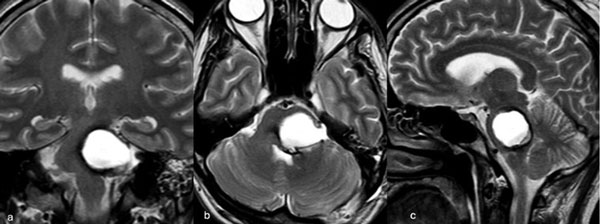

Figura 2. RM postquirúrgica de encéfalo. Se evidencia una exéresis completa, sin lesión de estructuras adyacentes. A) Imagen ponderada en T1 posterior a la administración de gadolinio, corte axial. B) Imagen ponderada en T2, corte axial.

Figura 5. RM postquirúrgica de encéfalo. Se evidencia una exéresis completa con hiperintensidad en T2 en regresión. A, B y C) Imágenes ponderadas en T2 en cortes coronal, axial y sagital, respectivamente.

Figura 8. RM postquirúrgica de encéfalo. Se evidencia una exéresis completa, sin daño del parénquima adyacente. A, B y C) Imágenes ponderadas en T2 en cortes coronal, axial y sagital, respectivamente.